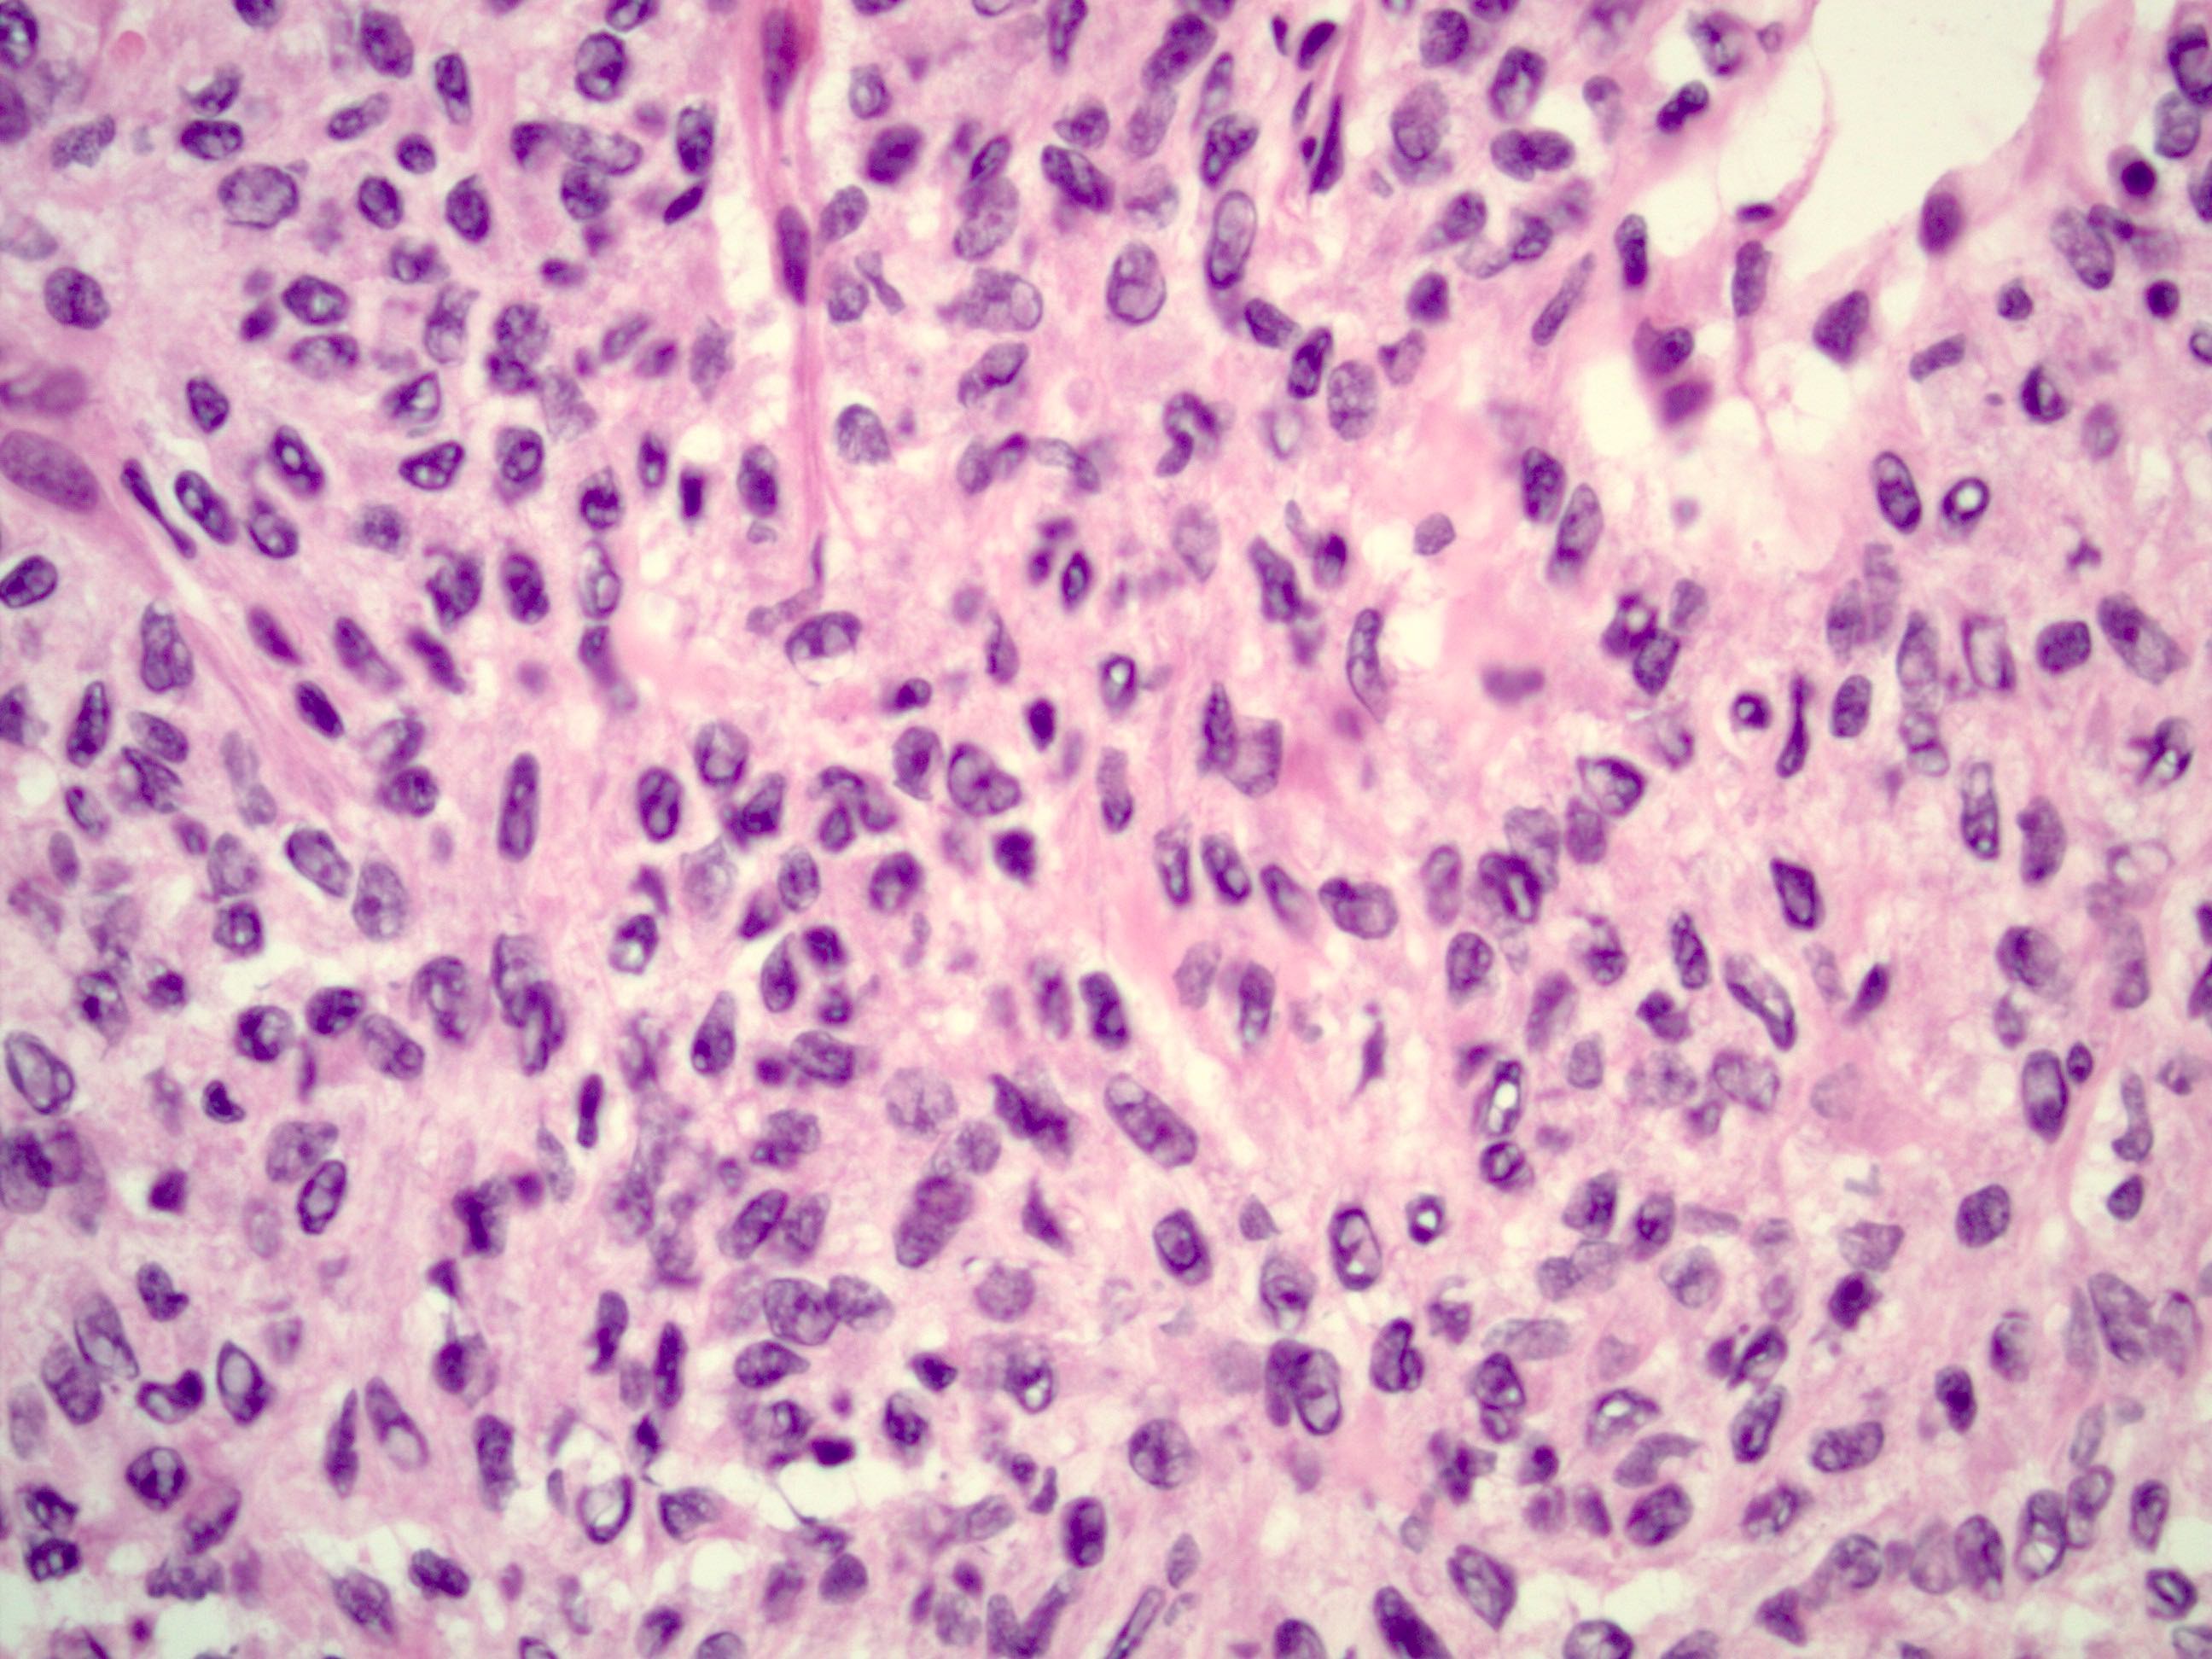

- Small, bland, cuboidal to polygonal cells with scant cytoplasm and pale, uniform angulated and usually grooved nuclei (coffee bean)

- Various patterns, including diffuse (the most common), trabecular and corded, insular, microfollicular (resembling Call-Exner bodies of the Graafian follicles: small follicle-like structures filled with eosinophilic material) and macrofollicular (the least common)

- Usually a mixed growth pattern is seen

- Rarely can be seen with juvenile type; classification should be based on the predominant histology

- Luteinized adult type (such as during pregnancy): rare (1%) if extensive (> 50%), plump cells with moderate to abundant eosinophilic cytoplasm, conspicuous nucleoli, no nuclear grooves, myxoid or edematous stroma; may resemble steroid cell tumor

- Mitotic activity is usually not brisk (< 3/10 high power fields)

- Stroma is usually hypervascular with variable amounts of fibroblasts and theca cells

- Theca cell proliferation is considered a stromal response rather than a second population of tumor cells (granulosa - theca cell tumor)

- Can have a prominent fibrothecomatous stroma; need 10% granulosa cells to be classified as adult granulosa cell tumor, otherwise best classified as thecoma or fibroma with minor sex cord elements